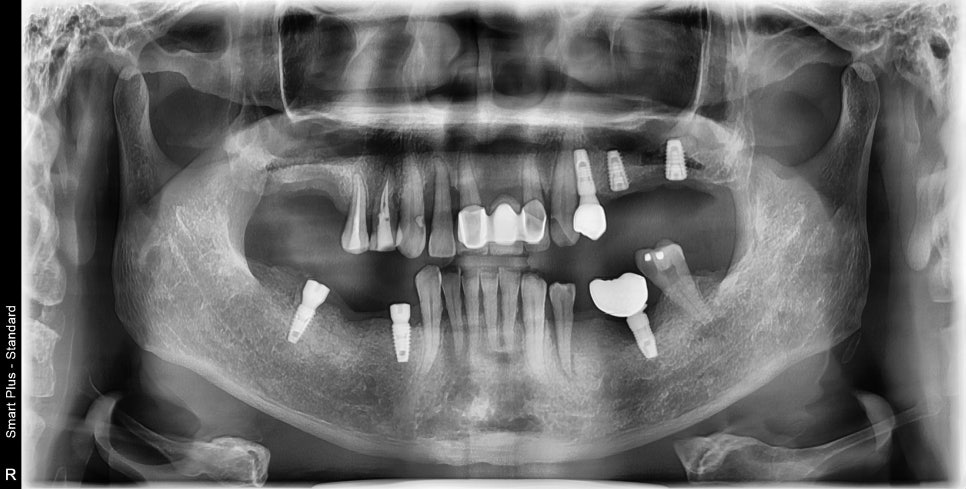

안녕하세요 무더위에 다들 고생이 많으십니다 오늘 보여드릴 케이스는 치아가 빠지고 나서 수년동안 방치한 결과 치료가 매우 힘들어진 케이스 입니다 오른쪽 아래를 보면 타 병원에서 심은 임플란트 옆에 솟구쳐 있는 치아가 보이실 겁니다 치아가 없는 상태로 오래지내게 되면 맞물리는 치아가 솟구쳐 오르게 됩니다 그래서 치아를...

오른쪽 아래를 보면 타 병원에서 심은 임플란트 옆에

솟구쳐 있는 치아가 보이실 겁니다

치아가 없는 상태로 오래지내게 되면

맞물리는 치아가 솟구쳐 오르게 됩니다

그래서 치아를 더 뽑아야 하거나 신경치료하고 씌워야 하는 경우가 발생하죠

이분은 어금니를 거의다 상실하시고

오랜기간 방치한 결과

수직고경상실이란 현상이 발생하였습니다

수직고경상실 이라는 것은 위아래로 얼굴이 짧아지는 것인데요

뒤에 어금니 들이 받치고 있기에 얼굴이 무너지지 않고 일정 길이를 유지하게 되는데

이때 어금니가 없다면 얼굴이 짧아지고 합죽해지게 됩니다

역으로 생각하면 없어진 어금니를 해 넣으면 다시 합죽한 얼굴의 길이감을 회복할 수 있죠.